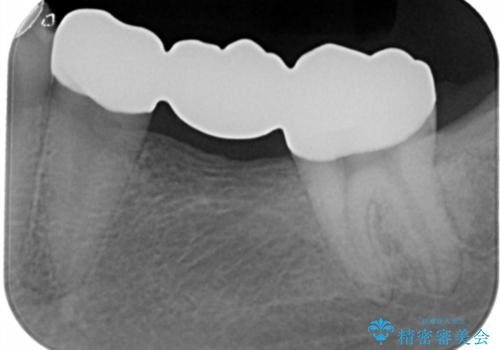

銀歯をやり変えたい フルジルコニアブリッジ

- 左下奥歯のブリッジのやり変え希望のため来院された患者様です。

支台歯部分はインレー形態でしたが強度や維持性を考慮しクラウン形態への変更を計画しました。

患者様の希望によりフルジルコニアブリッジを選択しました。

後ろの歯が前に倒れ込んでいましたが問題なく治療を終えることが出来ました。